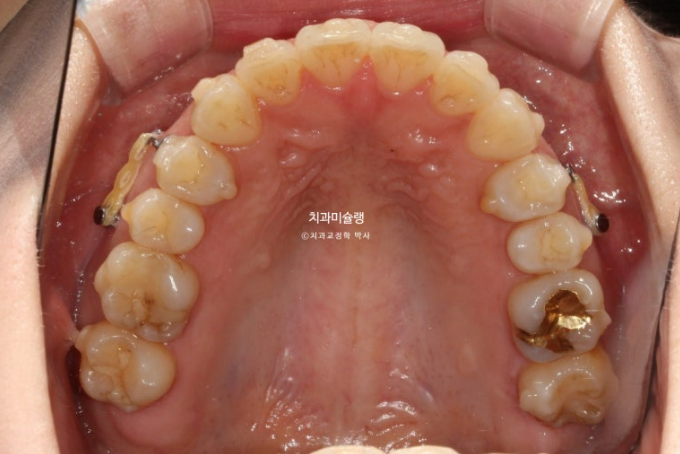

2년 전 교정치료를 위해 온 30대 환자분입니다. 파란 화살표 볼쪽으로 튀어나간 어금니들이 보입니다.

앞니뻗침으로 인한 돌출이 있고

좌측에는 가위교합이 소구치에 하나 대구치에 하나 총 2군데 있습니다.

아래 큰어금니는 안으로 쓰러져 있습니다.